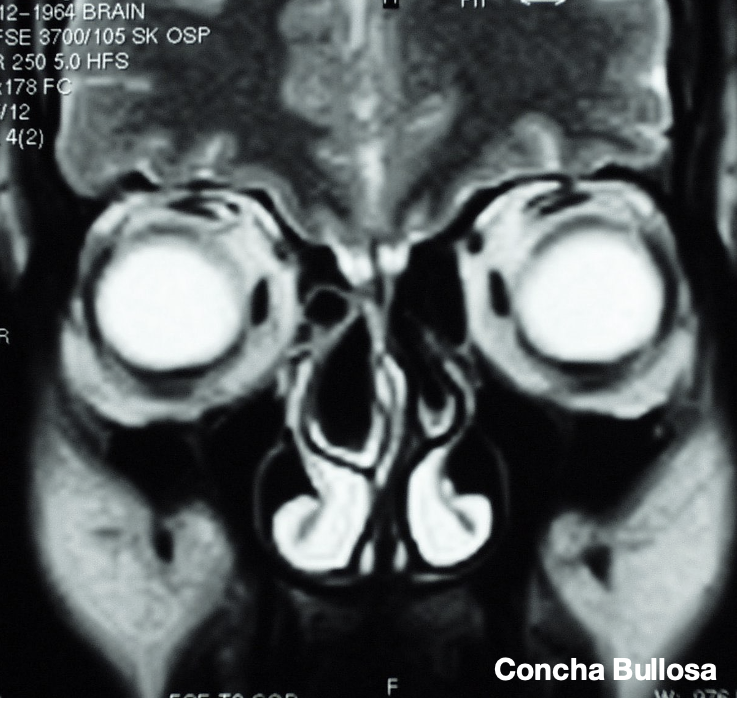

Uno studio retrospettivo indiano basato sulle TC di 75 pazienti (età 25-70 anni) affetti da sinusite cronica ha riscontrato una deviazione del setto nasale nel 66.6% dei pazienti seguita da ipertrofia della bulla ethmoidalis (46.6%) e dalla concha bullosa (una pneumatizzazione del turbinato medio) nel 40%.

Concha Bullosa: Turbinoplastica Mininvasiva

La Concha Bullosa ed il suo valore anatomo clinico nella patologia rinosinusale